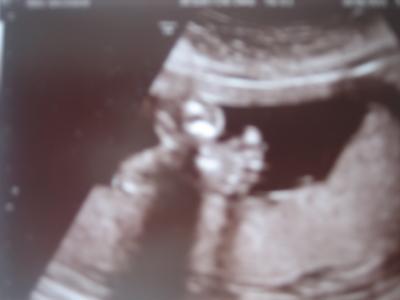

na ihr süßen...alles soweit gut bei euch?? waren gestern beim feinultraschall...hachjeee war das toll! 80 minuten durften wir unseren sohni anschauen und mein mann hat keinen ton rausgebracht weil er soooo gerührt war sie hat sich das herz, nieren magen leber, knochen und und und alles angeschaut und zwar gaaaanz genau und alles erklärt und alles ist einfach toll!!! wir haben einen kerngesunden prinzen (was man bisher beurteilen kann) und haben allen grund zum glücklich sein!! wir haben 10 bildchen mitbekommen und ohwehhh ich schwärme noch immer!! größe 22 cm gewicht 393 g laaange beine und er lebt schon heute auf großem fuß aber seht selbst

Bild zu mooorrrgäääään und bericht vom FU gestern - Forum für Oktober - Mamis